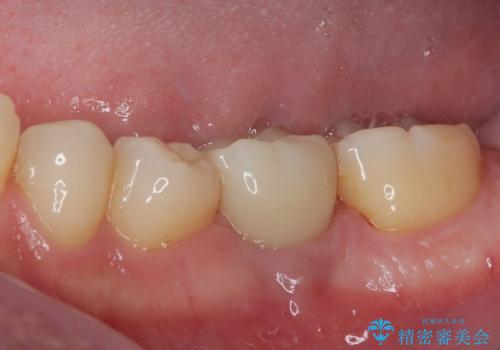

インプラント部は埋入とともに仮歯を装着し、同時に上顎奥歯の部分矯正を開始することとしました。

理想的な咬み合わせに改善した上で、インプラント補綴治療を行うこととしました。

部分矯正を行ったこと治療期間は長くなりましたが、違和感のない咬み合わせを達成することができました。